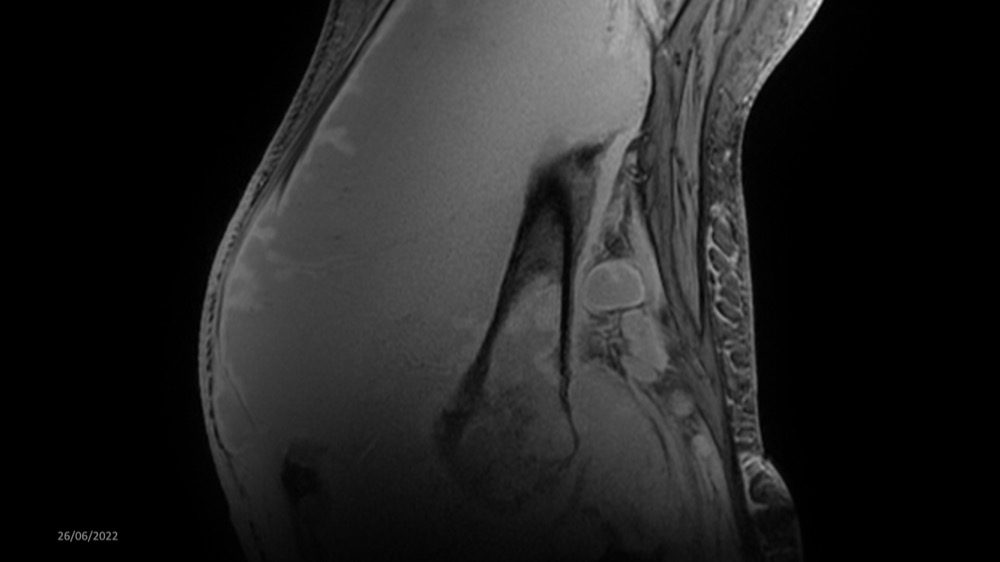

Reichert / Amar / Tordjman / Carlier 29/06/2022